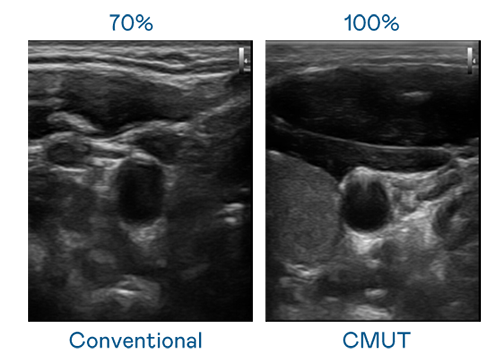

CMUT 技術是一種用電容式微機電元件來產生超音波訊號的技術。與傳統 PZT 壓電式技術相比,CMUT 頻寬增加 30%,更寬頻的超音波訊號讓影像解析度大幅提升,是實現高影像品質醫療超音波掃描、促進精準醫療發展的關鍵技術。

大頻寬帶來超清晰影像

超音波影像的解析度高低,首先取決於探頭能發出的訊號頻寬。PA官方网站 CMUT 可提供高清晰的超音波訊號,提供高頻寬、高靈敏度、影像紋理細節更高的超音波影像,協助醫護人員縮短影像判讀時間及利用精準的醫療影像進行診斷。